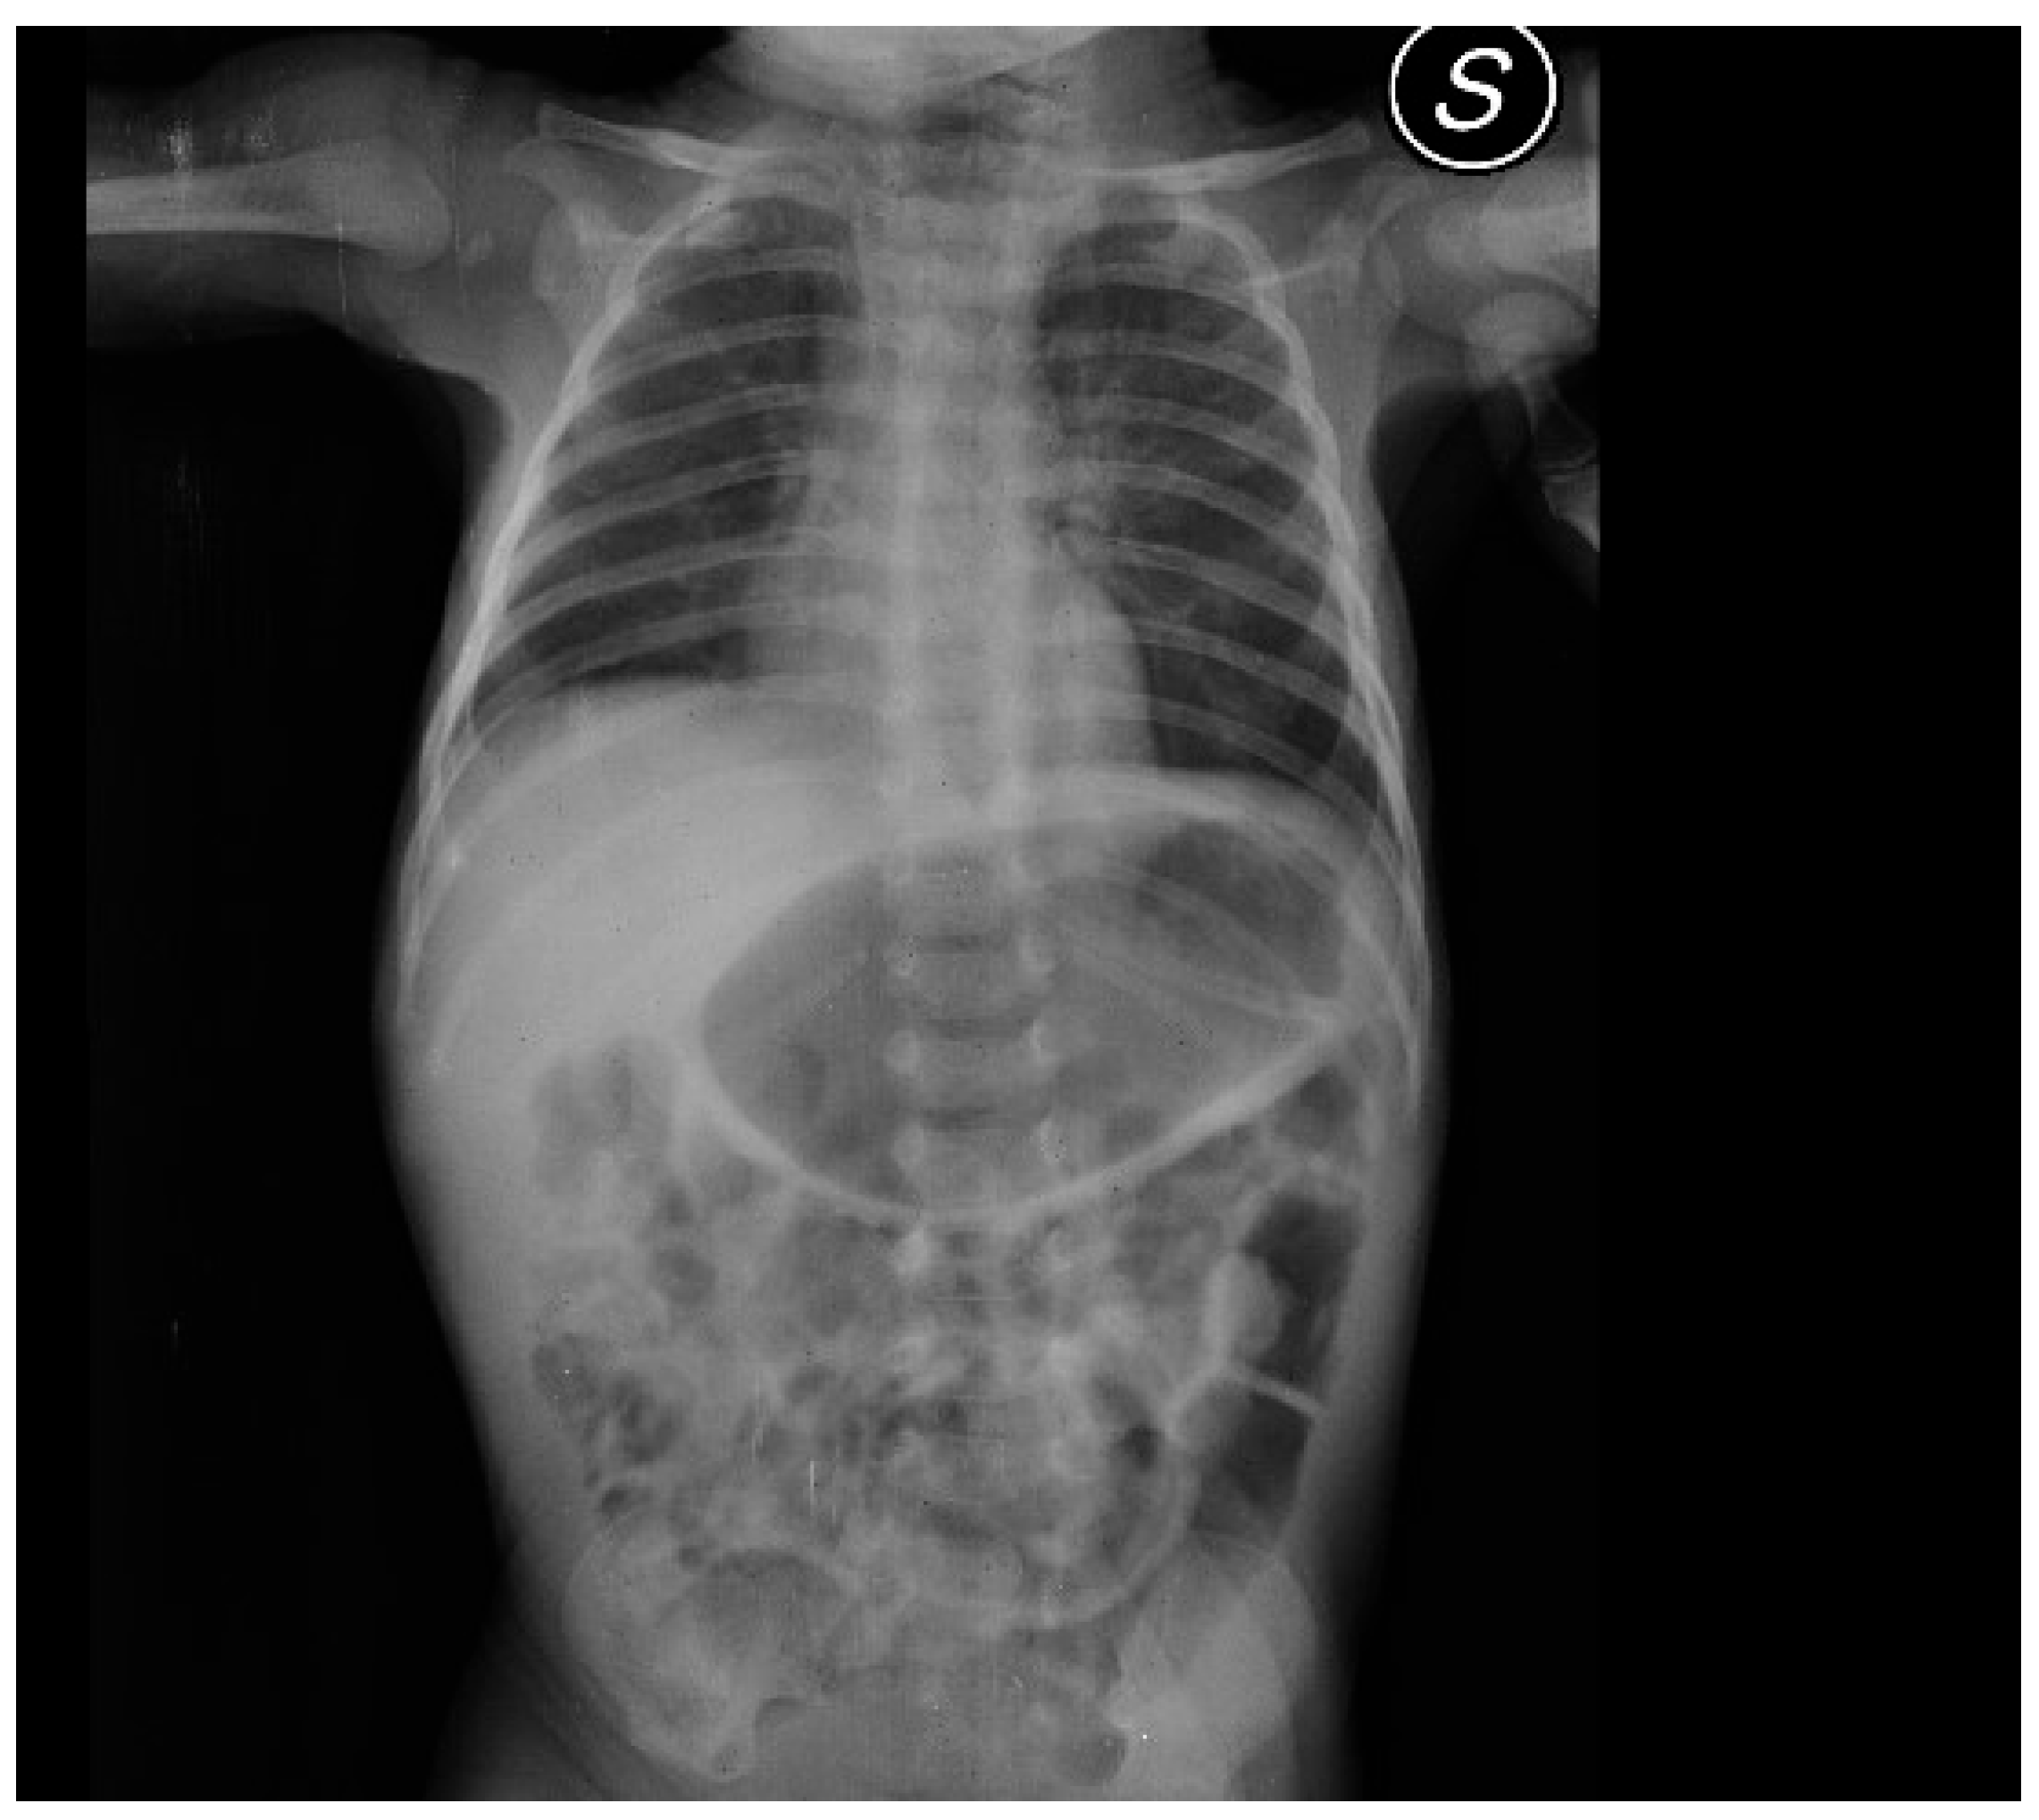

After admission, the infant presented with some projectile, non-bilious vomiting. An abdominal X-ray proved a marked gastric distension (Figure 1). An abdominal ultrasound (US) displayed a thickened pylorus with a wall thickness of 5.7 mm and a length of 17.5 mm (Figure 2). A diagnosis of hypertrophic pyloric stenosis was made.

Figure 1. Abdominal X-ray showing gastric distension. The radiograph illustrates marked gastric distension, consistent with pyloric stenosis.